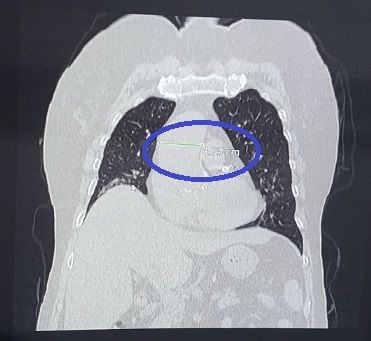

위 CT사진은 저의 모친이 2023년 11월 16일에 병원에서 찍은 폐CT사진인데요.

대동맥이 4.75cm 정도로써 일반인보다 상당히 굵다고 하던데요.